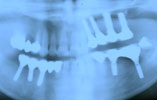

CASE8

上顎、下顎に多数の歯が抜けている場合 審美的・機能的に回復

インプラント埋入前

インプラント埋入後

インプラントに

セラミッククラウンを装着

術前

術後

上顎、下顎とも多数欠損により、長い間上手く噛めませんでした。CT撮影後、上顎に4本、下顎に5本のインプラントを埋入し、

固定式のブリッジを装着することにより、審美的、機能的回復をいたしました。